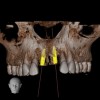

Fig 2. CBCT images: axial (Fig 2) and cross-sectional (Fig 3) views, and 3D reconstruction view (Fig 4) with virtually planned implant Nos. 8 and 9.

Figure 2

Fig 3. CBCT images: axial (Fig 2) and cross-sectional (Fig 3) views, and 3D reconstruction view (Fig 4) with virtually planned implant Nos. 8 and 9.

Figure 3

Fig 4. CBCT images: axial (Fig 2) and cross-sectional (Fig 3) views, and 3D reconstruction view (Fig 4) with virtually planned implant Nos. 8 and 9.

Figure 4

For dental implant-based treatment, the planning phase begins with collection of basic data sets; this is digital touchpoint 1. It includes: (1) a cone-beam CT (CBCT) to view edentulous areas or failing tooth structure, bone, and anatomic landmarks under the soft tissue (Figure 2 through Figure 4); and (2) an intraoral optical scan (IOS) or a scanned model or impression to record the soft tissue and tooth anatomy (Figure 5). The superimposition of the digital imaging and communications in medicine (DICOM) files from the CBCT and the standard tessellation language (STL) files from the IOS allows visualization of how bone, dental structures, and soft tissues relate. Both digital data points are key to implant selection and determining the surrounding bone-grafting needs. An initial treatment plan includes determining the desired implant manufacturer/implant design, size, and positions; these decisions remain the responsibility of the clinician (restoring and surgical team members) and not the technician or planning team.